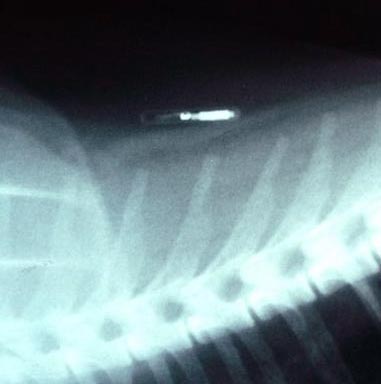

Seamus underwent emergency surgery, and doctors extracted a 4-pound, 3-ounce tumor from the dog. They used four drains to remove fluid from the area in which the tumor had developed. The veterinarian informed the dog's owner, Howard Gillis, that there had been two microchips embedded in Seamus – one presumably inserted by the dog's breeder when Seamus was only 9 months old. The chips were both located in and around the tumor.

Albrecht told the story of another dog, a 5-year-old Yorkshire terrier named Scotty that was diagnosed with cancer in Memphis, Tenn. Scotty developed a tumor between his shoulder blades, in the same location where the microchip had been implanted. The tumor the size of a small balloon – described as malignant lymphoma – was removed. Scotty's microchip was embedded inside the tumor.

In Scotty's December pathology report, the doctor wrote: "I was previously suspicious of a prior unrelated injection site reaction" beneath the tumor. "However, it is possible that this inflammation is associated with other foreign debris, possibly from the microchip."

The doctor said the chip was coated with a translucent material to keep the microchips from moving around the body. "This coating could be the material inciting the inflammatory response," he wrote.